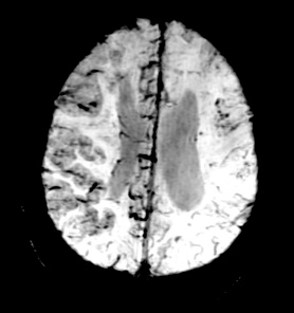

Neuroimaging

All basic MRI for anatomical images (like T2WI, T1WI, GRE, etc), Neuro perfusion, DSC-based perfusion, DCE-based perfusion and permeability, Cerebral blood flow (2D and 3D ASL), Advanced less-distorted DWI, Selective excitement. DTI (B-value ranges from 0 -10000 s/mm2, directions 256) and fMRI (NordicNeuroLab fMRI and Visual system).

Click images for larger view and description

• ADC